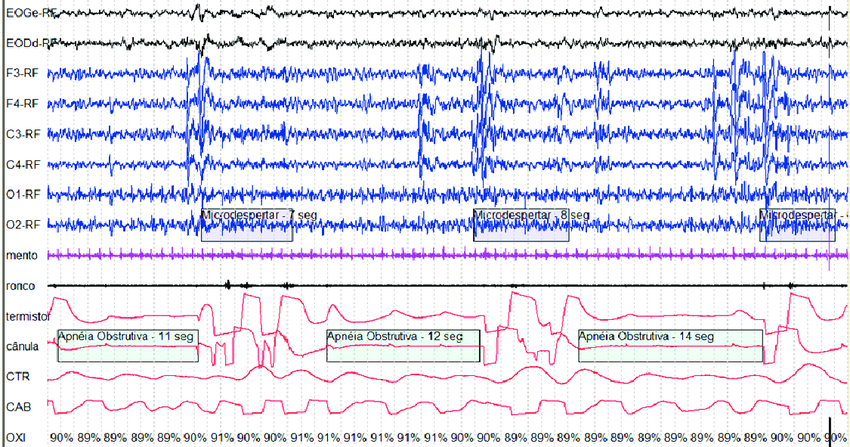

Para criar esse mapa detalhado, nós, profissionais, analisamos diversos canais de informação. A polissonografia registra sua atividade cerebral (Eletroencefalograma), o que nos permite identificar os diferentes estágios do sono (como N1, N2, N3 e o famoso sono REM). Além disso, ela monitora o movimento dos seus olhos (Eletrooculograma), a atividade dos seus músculos (Eletromiograma), o ritmo cardíaco (Eletrocardiograma), o fluxo de ar pelo nariz e boca, seu esforço respiratório (através de cintas no tórax e abdômen) e os níveis de oxigênio no seu sangue (oximetria).

Acima de tudo, a polissonografia serve para diagnosticar com precisão os distúrbios respiratórios do sono. O mais conhecido e comum deles é a Apneia Obstrutiva do Sono (AOS). Durante o exame, conseguimos identificar e contar os eventos de apneia (parada total da respiração) e hipopneia (redução do fluxo de ar). Assim, podemos classificar a gravidade da sua apneia (leve, moderada ou grave) e, consequentemente, definir o melhor e mais confortável tratamento para o seu caso.